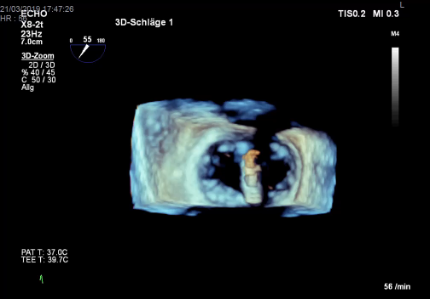

Im Oktober 2017 wurde in unserer OP-Gruppe der Hybrid-OP in Betrieb genommen. Dieser Herz-OP-Saal ist mit einer uniplanaren Fluoroskopie-Anlage, einem „high-end“ Echokardiographiegerät und hochauflösenden Monitoren ausgerüstet. Der Hybrid-OP wird von der Herzchirurgie, Kardiologie, Gefäßchirurgie und Interventionellen Radiologie genutzt.

Zur Steuerung der Interventionen werden Fluoroskopie, transösophageale Echokardiographie und Hämodynamik auf großen, hochauflösenden und für alle gut einsehbaren Monitoren wiedergegeben.

Während TAVIs in leichter Sedierung durchgeführt werden, benötigen andere Interventionen eine Allgemeinanästhesie: Transapikale oder trans-subclavia TAVI, transkatheter edge-to-edge repair der Mitral- und Trikuspidalklappe, transkatheter Mitralklappen- und Trikuspidalklappenersatz oder extra-anatomische bi-cavale Klappenimplantation (TricValve). Bei den herzchirurgischen transkatheter Eingriffen wird das Echo-Guidance von Mitarbeiter:innen unserer Abteilung bewerkstelligt.

Bildergalerie der Forschungsgruppe